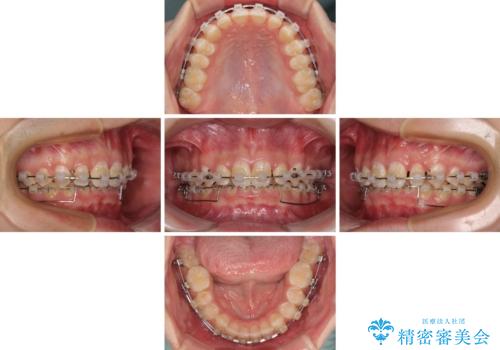

- クリアブラケット

下顎前歯が全て隠れてしまうほどの深い咬合で、左右の奥歯は1歯対1歯で咬み合う状態でした。

前方に移動している上顎臼歯を補助装置にて遠心移動させることで1歯対2歯の臼歯咬合を目指し、同時に深い咬合を改善していくこととしました。

このような咬み合わせの場合、治療期間は2年以上がかかることが一般的で、3年程度かかることもありえるケースです。

強く深い咬み合わせにより下顎装置は頻繁に脱離するため、治療期間が長くなりますが、予定通りに終了させることができました。